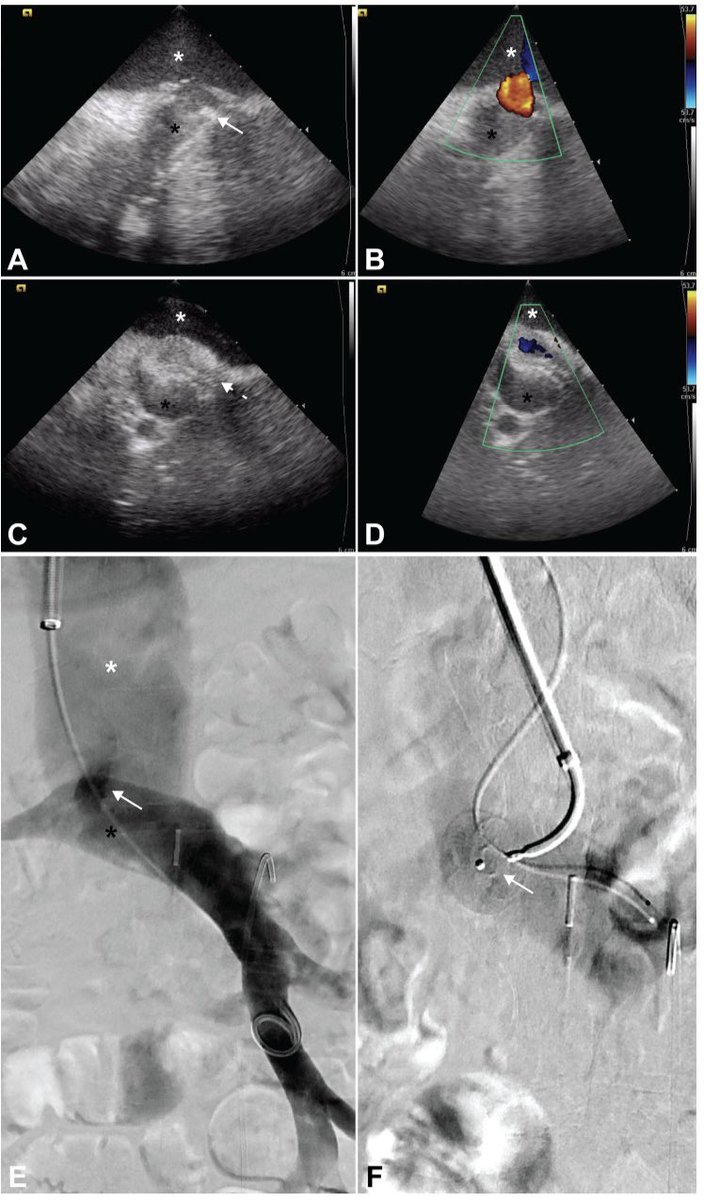

Successful Direct intrahepatic portocaval shunt using gun sight technic! Altered hepatic venous anatomy precluded standard TIPS

David Léon MD tweet mediaDavid Léon MD tweet mediaDavid Léon MD tweet mediaDavid Léon MD tweet media